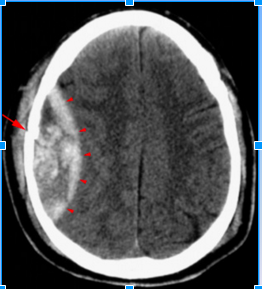

- Epidural hematoma is usually associated with what?

- What is the injury that results from this?

- Where does the blood collect?

- Usually associated with a skull fracture

- The fractured bone lacerates a dural artery or a venous sinus

- The blood from the ruptured vessel collects between the skull and dura

- On the CT, the hematoma forms a what?

- It is usually uniformly ____ _______but may contain hypodense foci due to active bleeding.

- hyperdense biconvex mass

- high density